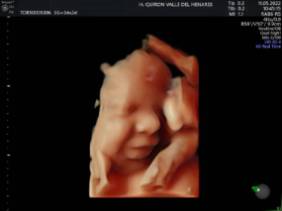

El Hospital Quirónsalud Valle del Henares incorpora un nuevo ecógrafo con tecnología 5 D

El Hospital Quirónsalud Valle del Henares ofrece la posibilidad de realizar ecografías gestacionales 5D. Este tipo de exploración permite obtener una imagen muy realista del bebé y se puede realizar en cualquier etapa de la gestación -aunque lo recomendado es realizarla entre las semanas 28 y 32 de gestación, ya que técnicamente es el mejor momento y es mucho más probable obtener imágenes de buena calidad-.

Al final de la prueba, se entrega a la familia un informe de la ecografía y un soporte digital que contiene las imágenes y los vídeos realizados. Las ecografías 4D y 5D son también llamadas emocionales por la explosión de sensaciones que genera cuando la madre ve por primera vez la imagen del bebé que espera.

"Realizar esta ecografía con nuestro equipo de diagnóstico prenatal tiene un valor añadido -señala la Dra. Rocío Vellido Cotelo, Jefa Asociada de Ginecología y Obstetricia del Hospital Quirónsalud Valle del Henares, dado que quien realiza la prueba es un especialista en la materia, siempre se completa la exploración con un examen morfológico y de perfil biofísico fetal, que permita valorar el estado de bienestar del bebé más allá de la captura de videos y fotografías".